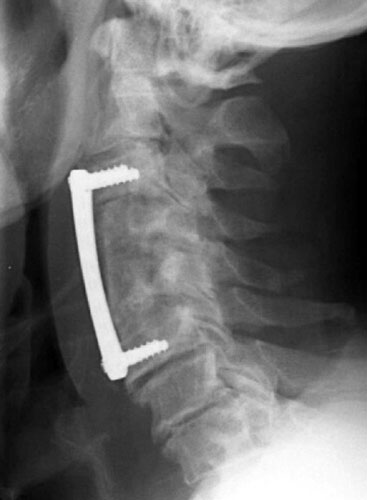

Immediate post-op radiograph demonstrate good position of the graft and fixation plate.